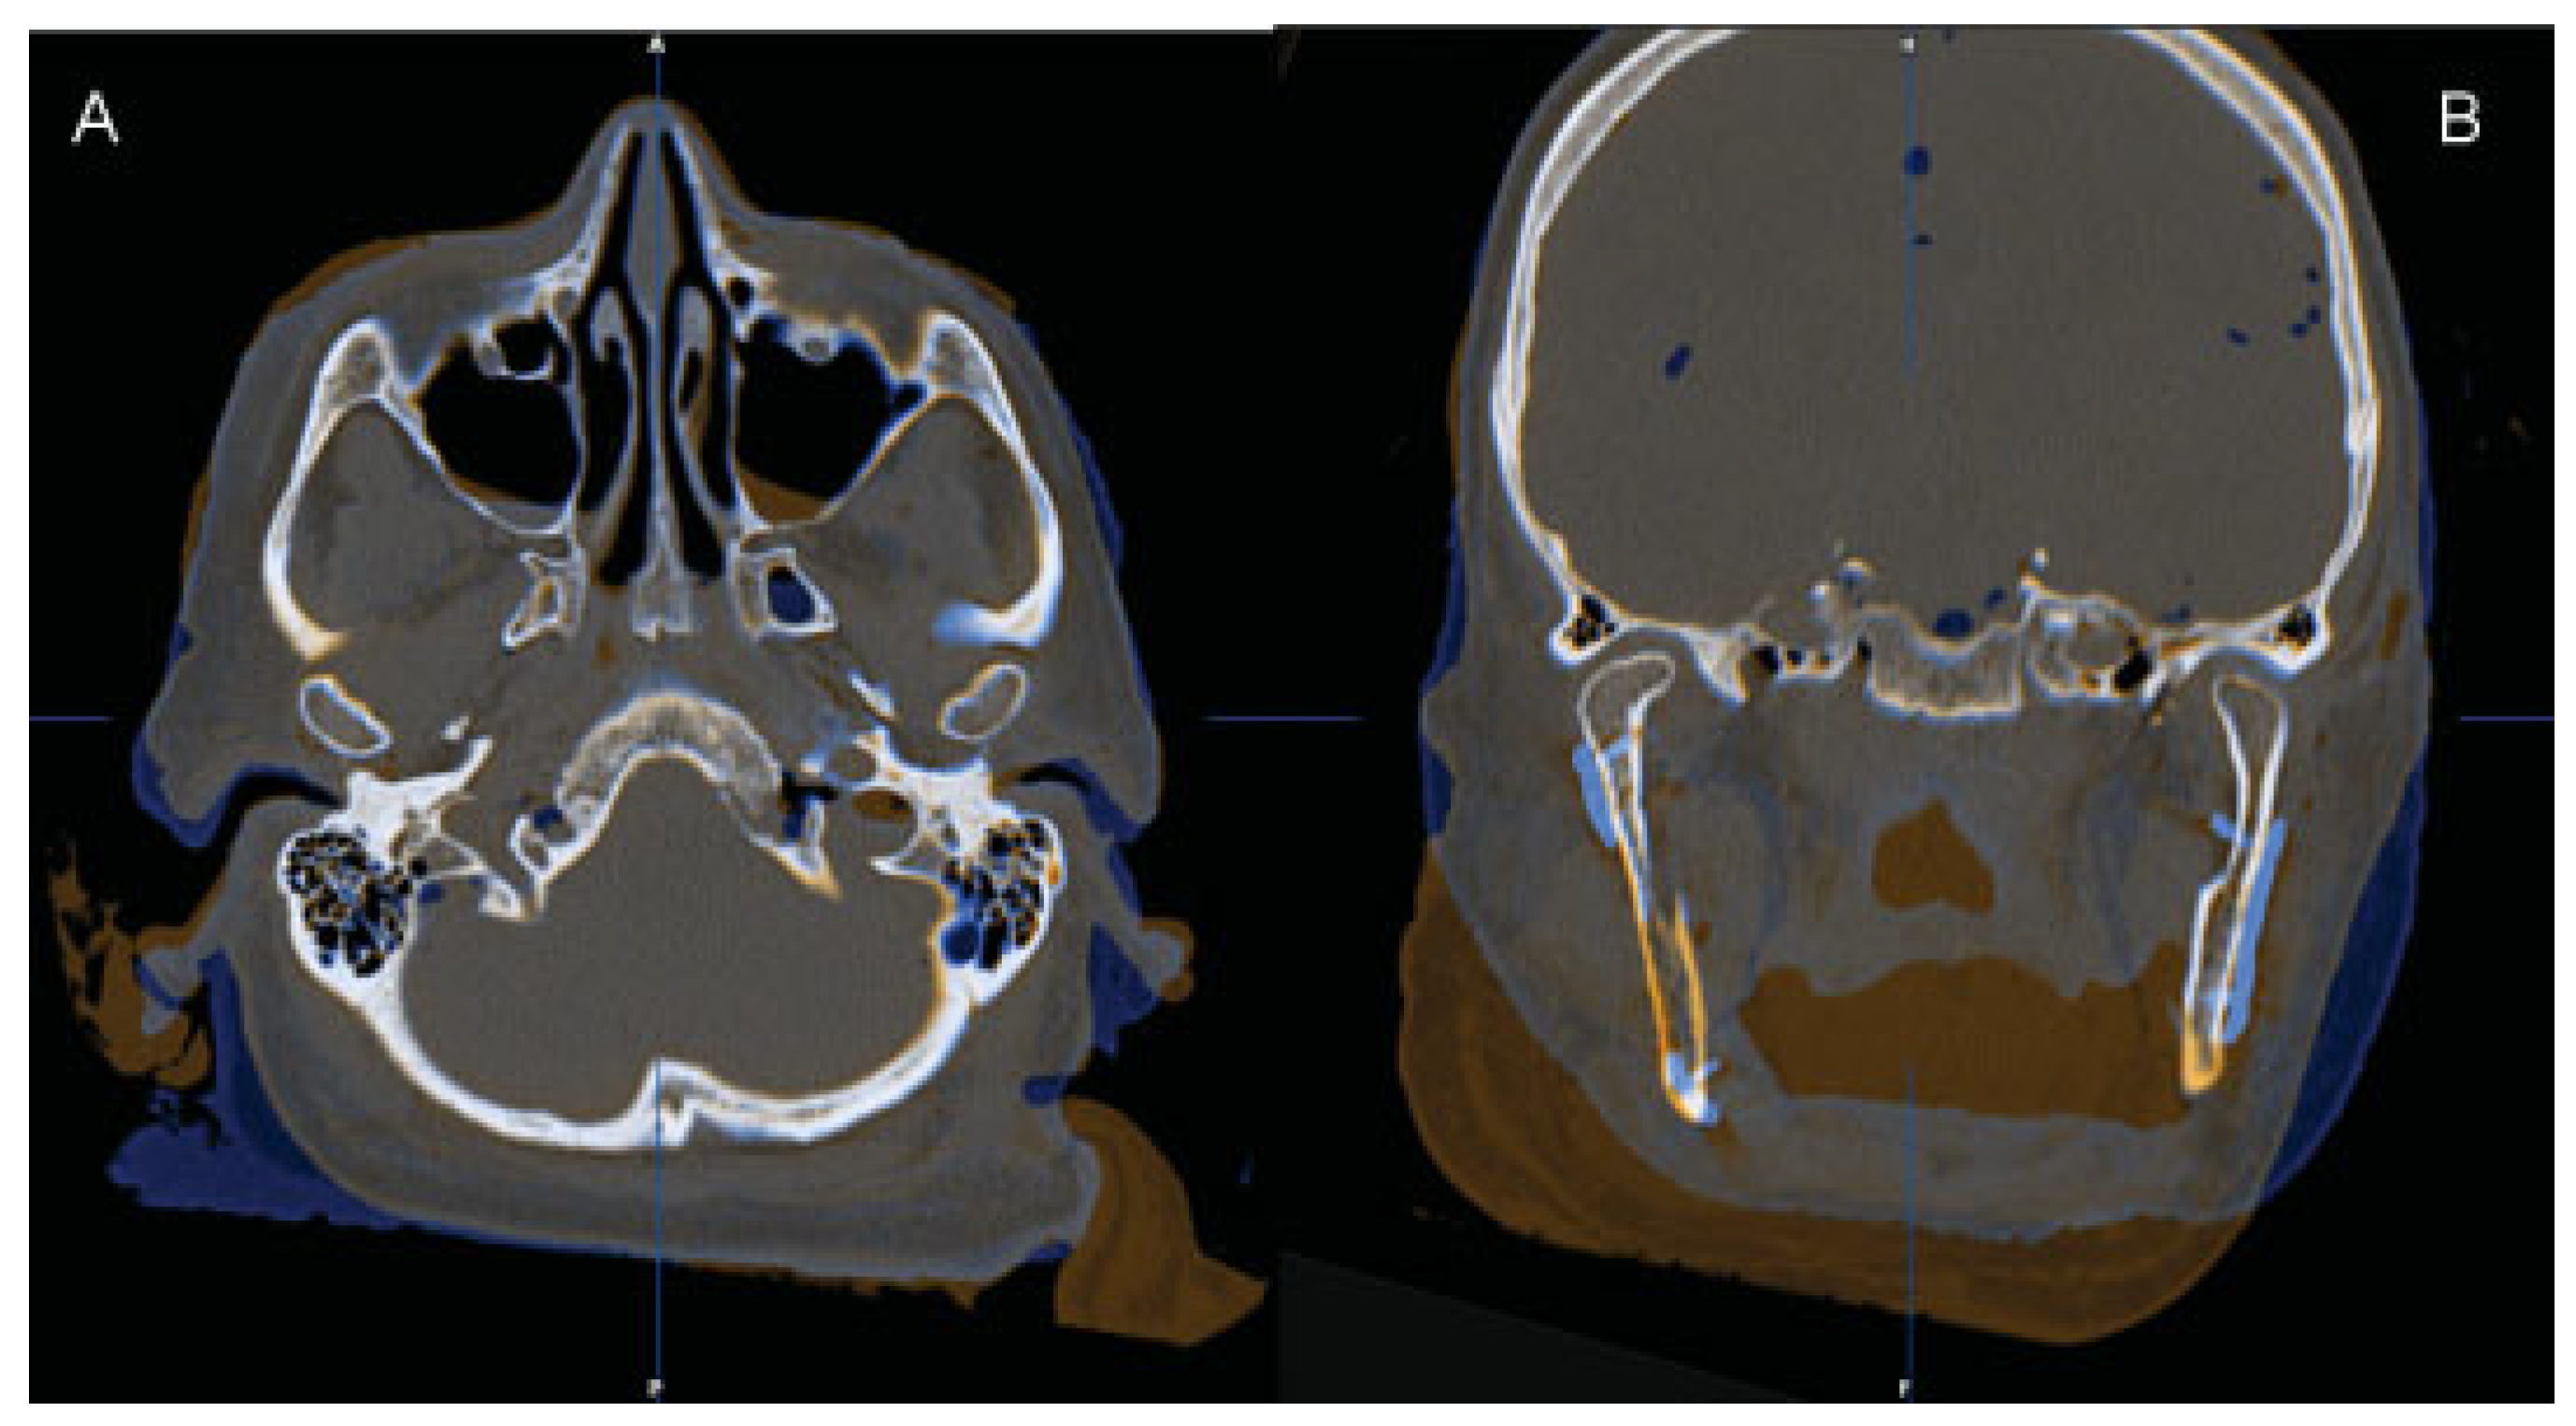

The postoperative CT also shows an almost perfect alignment of the six fibula segments along the CAD/CAM-fabricated reconstruction plate and close contact between the bone segments (Figure 11). The lengths of the screws had been determined virtually. In the clinical setting, bicortical screws were placed in the residual mandible and monocortical screws in the fibula segments exactly as planned.

Figure 11. Postoperative CT scan of the reconstructed mandible showing good alignment of the six fibula segments along the CAD/CAM-fabricated reconstruction plate as well as close contact between the bone segments (axial view).